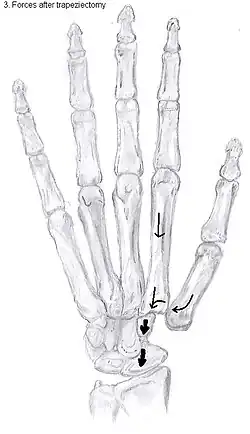

Trapeziectomy

During trapeziectomy,[30] the trapezium bone is removed without any further surgical adjustments. The trapezium bone is removed through an approximately three centimeter long incision along the lateral side of the thumb. To preserve surrounding structures, the trapezium bone is removed "by splitting" it into pieces.

An empty gap is left by the trapeziectomy and the wound is closed with sutures. Despite this gap, no significant changes in function of the thumb are reported.[27] After the surgery, the thumb will be immobilized with a cast.

Disadvantages include inability to flatten the hand.[27] Additionally, the stress on the CMC joint is now spread over the adjacent joints, those joints are more likely to develop osteoarthritis.[34]